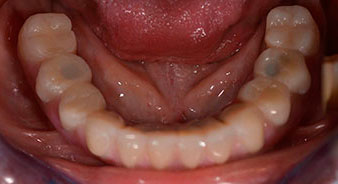

Una vez transcurrido el tiempo necesario para la integración ósea, puede llevarse a cabo la impresión definitiva del implante para realizar la prótesis definitiva de manera acorde (figs. 19 y 20). En este paso, el responsable del tratamiento y el paciente pueden decidir conjuntamente si es preferible un revestimiento cerámico o plástico y una estructura de zircón o de metal. En este caso, dado que el pronóstico de la dentición del maxilar superior era poco claro y la pieza dental 24 estaba elongada, el equipo del Dr. Pascu se decidió por un revestimiento de plástico, ya que, por lo general, es mucho más fácil de ajustar y puede adaptarse a la nueva situación del maxilar superior.